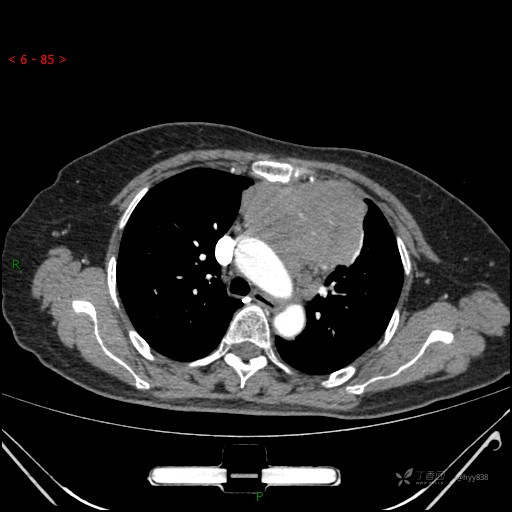

简要病史:患者诉3月余前患新冠肺炎,出现持续性胸闷,活动后可缓解,无胸前区压榨感,无畏寒发热不适,无胸痛咯血、呼吸困难,无恶心、呕吐,无腹痛、腹胀、腹泻等不适,未予以重视,未行特殊处理。患者胸闷持续存在,为进一步诊治,3天前于本院查胸部CT提示前纵膈团块状软组织密度影,肿瘤性病变可能,心包积液,左上肺磨玻璃结节,右下肺增殖灶可能建议进一步检查。门诊以“前纵膈占位” 收入我科。 患者本次起病来精神、食欲、睡眠尚可,大小便正常,体力、体重无明显变化。

辅助检查:CT

动脉期

静脉期